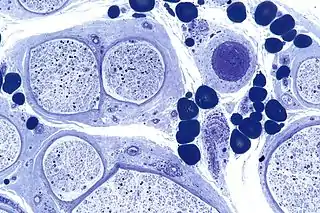

![]() Micrografía que muestra una neuropatía periférica vascular. Plastificada. Tinción con azul de toluidina. | ||